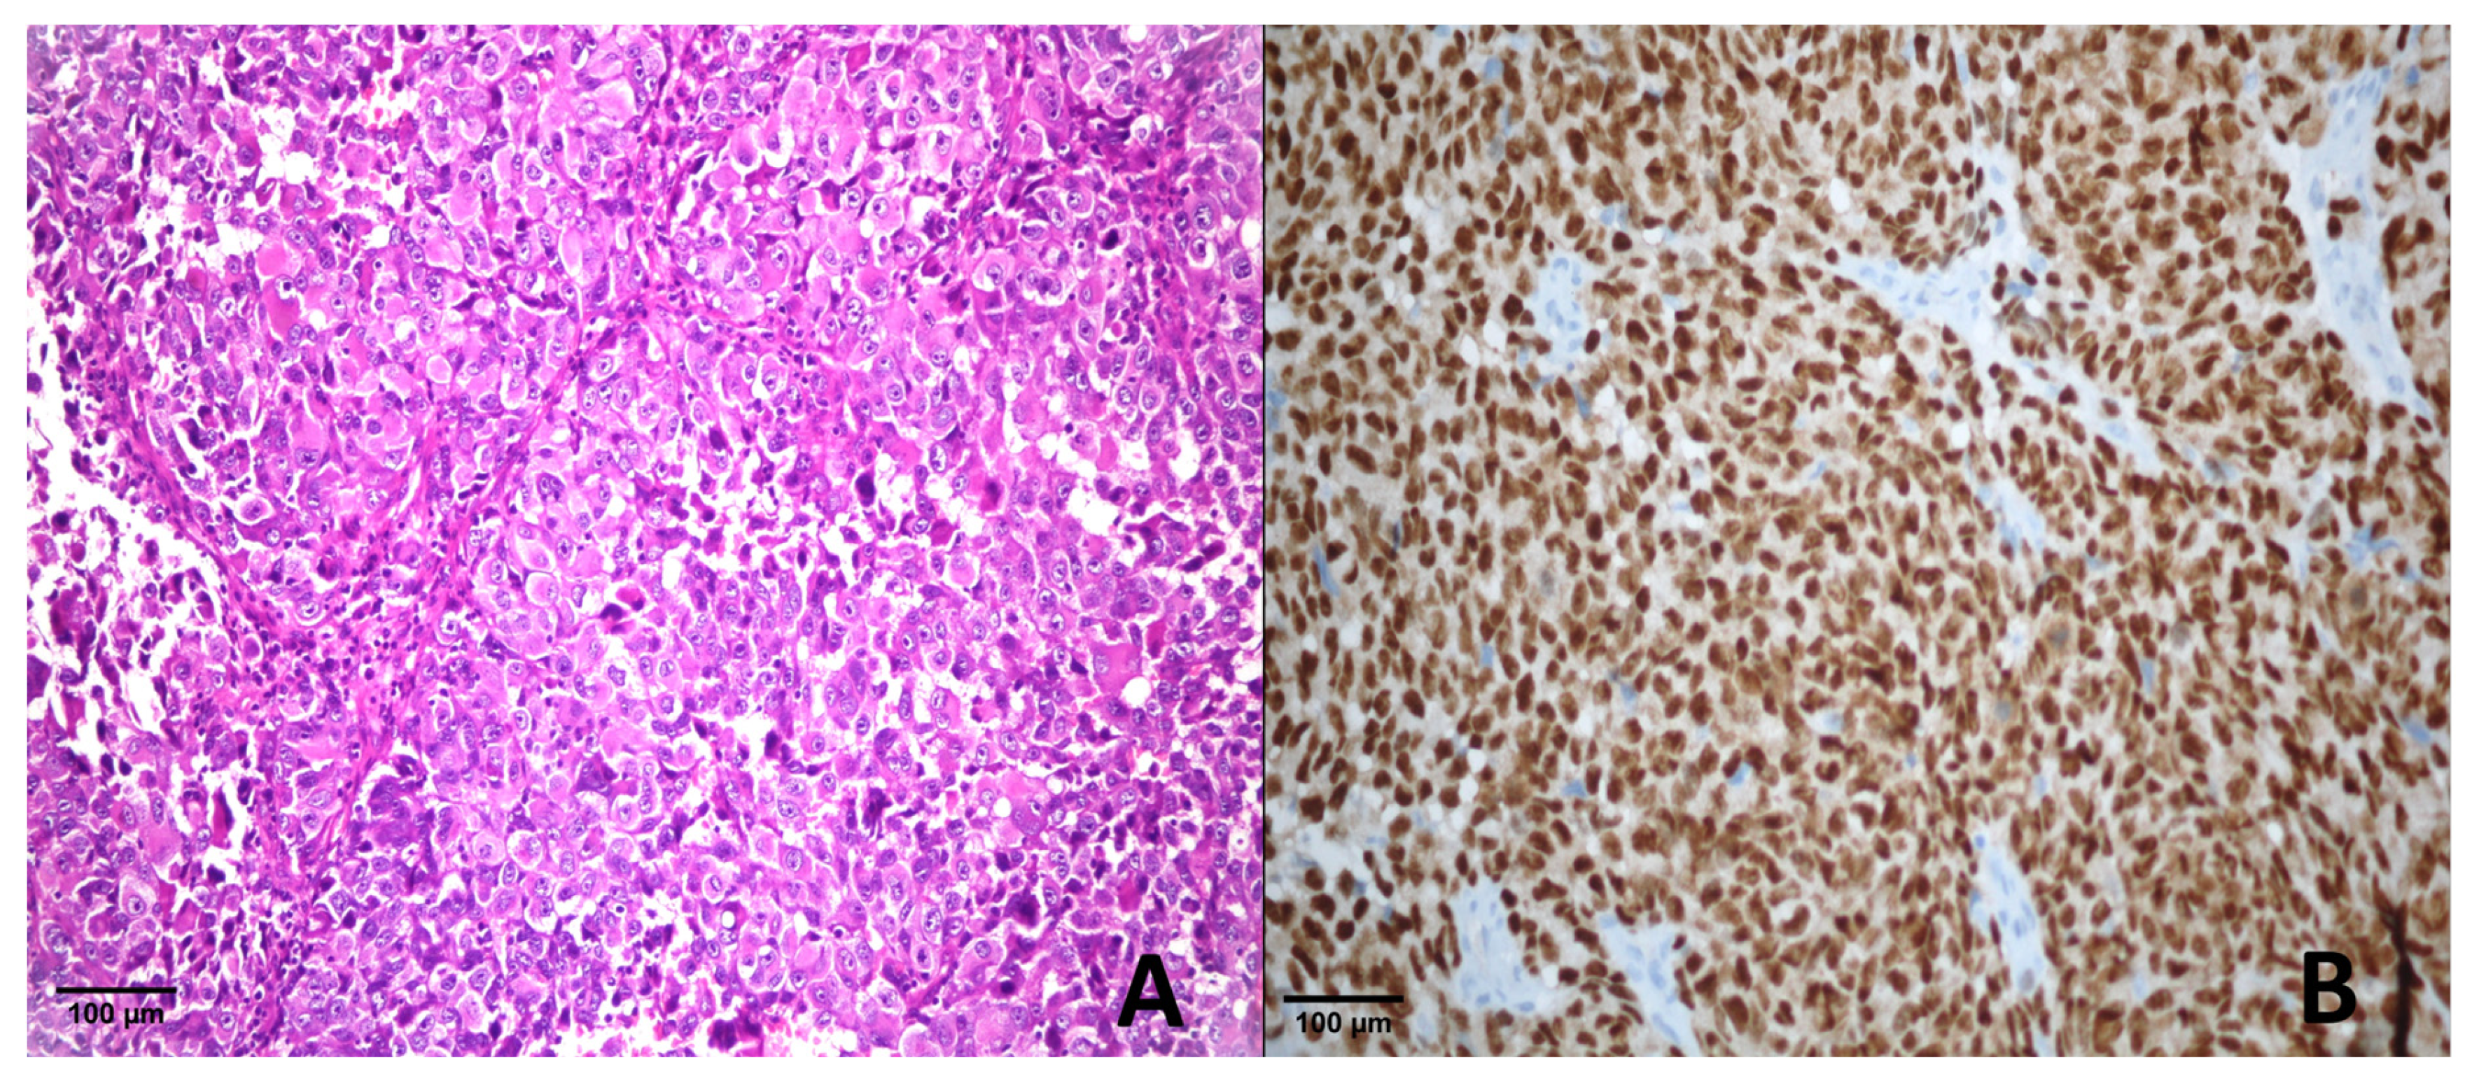

4.4.1. Metastatic Melanoma

| +4 | 8/12 | 35/40 | 1/27 | 0/5 | 0/15 | 0/23 | 0/11 | 0/12 |

| +3 | 2/12 | 3/40 | 0/27 | 0/5 | 0/15 | 0/23 | 0/11 | 2/12 |

| +2 | 2/12 | 1/40 | 0/27 | 0/5 | 0/15 | 0/23 | 0/11 | 0/12 |

| +1 | 0/12 | 0/40 | 2/27 | 0/5 | 1/15 | 0/23 | 1/11 | 0/12 |

| 0 | 0/12 | 1/40 | 24/27 | 5/5 | 14/15 | 23/23 | 10/11 | 10/12 |